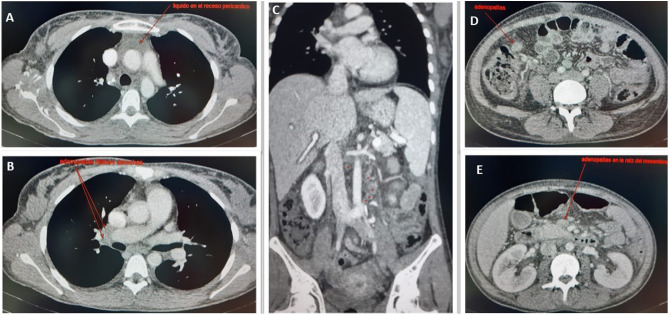

Evolucionó de forma desfavorable en planta, tanto clínica como analíticamente (Appendix B) por lo que se inició piperacilina-tazobactam y doxiciclina. Al 4.° día de ingreso presentó shock (PA: 70/40 mmHg; FC:136 lpm) y oligoanuria, que no respondía a fluidoterapia por lo que se realizó nueva TC toracoabdominopélvica (Appendix B) que mostró múltiples adenopatías, sobre todo en raíz de mesenterio y FID, leve esplenomegalia, líquido en el receso pericárdico, edema periportal y ascitis leve-moderada. Ingresó en UCI con tratamiento con piperacilina-tazobactam, linezolid, ganciclovir y anfotericina B liposomal, a la espera de resultados microbiológicos. Ante la sospecha de shock séptico de origen abdominal-ginecológico, se realizó una laparotomía exploradora, que resultó sin hallazgos patológicos, salvo adenopatías mesointestinales y en mesocolon, que se resecaron.

Figura 1.

Ganglios linfáticos con linfoadenitis necrosante: necrosis isquémica con vasculitis necrosante (A), vasos periganglionares con trombo rojo (B), hiperplasia folicular con reacción inmunoblástica (C), plasmocitosis e histiocitosis sinusal (D). Presencia de ocasionales microgranulomas (E) (flecha). Inmunohistoquímica positiva para SARS-CoV-2 (F).